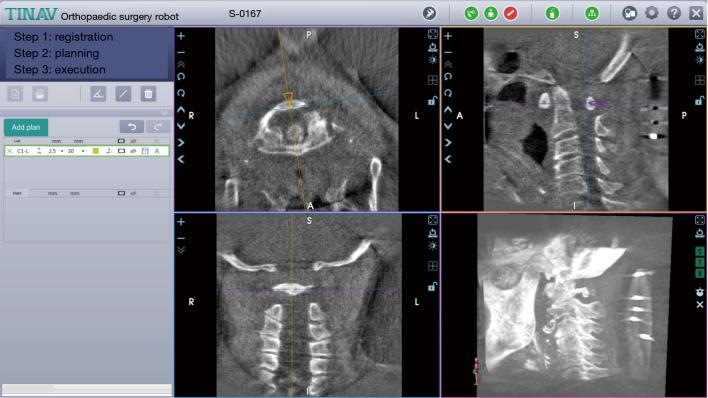

DASM is rare but potentially dangerous. Its diagnosis is made based on clinical manifestations combined with radiological imaging examinations, especially computed tomography (CT) scan and magnetic resonance imaging (MRI). While C1L is the most common surgical method, PFEC1L is a new feasible and safe therapeutic option with comparable good outcomes and the advantage of being minimally-invasive. To our knowledge this is the first report that PFEC1L was applied for DASM treatment.

DASM罕见但具有潜在危险性。其诊断基于临床表现并结合影像学检查,尤其是计算机断层扫描(CT)和磁共振成像(MRI)。虽然C1L是最常见的手术方法,但PFEC1L是一种新的可行且安全的治疗选择,具有相当好的效果且具有微创优势。据我们所知,这是首次报道将PFEC1L应用于DASM治疗。